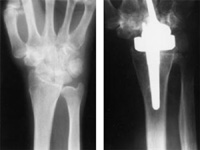

X-ray of a wrist with osteoarthritis before (left) and after (right) wrist replacement surgery using a two-part metal and polyethelene implant.

Reproduced with permission from Carlson JR, Simmons BP: Total Wrist Arthroplasty. J Am Acad Orthop Surg 1998;6:308-315.